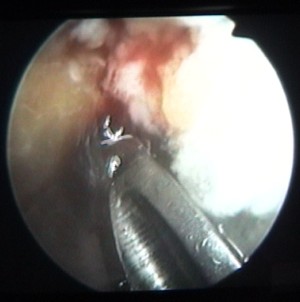

on voit la tête de la vis au milieu de la clé plate |

et le corps de la vis en-dessous |

cette vis sert à attacher le ligament |

et elle est maintenant vissée à fond |